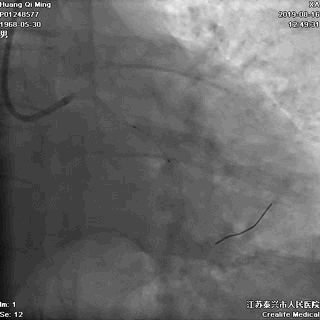

术后即刻效果满意

CCTA的指导价值

药物洗脱球囊最核心的操作要领:一是充分的斑块预处理,二是药物球囊迅速到达目标病变位置,从而实现最有效的药物定点释放。其中,CCTA的评估功能不容小觑。结合上面的病例,术前CCTA检查的必要性如下:

1、明确了LAD病变位于血管的中远段,比较弥漫,病变段血管整体偏细,是应用药物球囊的适应症;

2、根据CCTA检查的结果,知晓病变的情况,预先准备好相应型号的药物洗脱球囊;

3、病变段血管为局灶性钙化,提示病变的预处理应该会很顺利;

4、病变近段的血管较直,相对健康,药物球囊入路通畅;

5、左主干无钙化,前分叉正常,为选用7F指引导管和/或使用延长导管提供了机会。

一句话,CCTA提示LAD中远段的小血管病变,可以使用药物洗脱球囊处理(给术者吃了颗定心丸)。